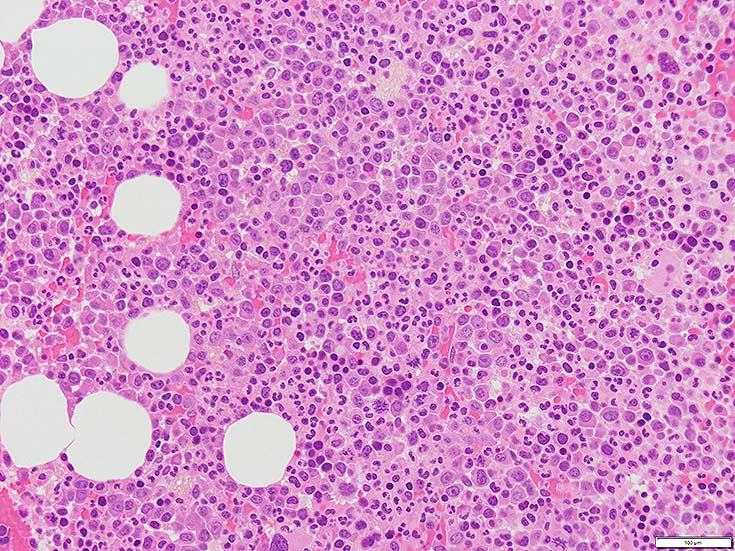

初診時の骨髄組織所見

thumb nail画像のクリックで大きな画像がみられます.

HE染色および, Naphtol-ASD-CAE染色した骨髄クロット組織標本-->Naphtol-ASD-CAE染色, 載せガラス法のページをみる.

70-80%のhypercellular marrow. 3系統造血細胞が認められる. Naphtol-ASD-CAE染色で赤色にそまる顆粒球系細胞増生が顕著な骨髄組織.

promyelocytesなど幼若顆粒球系細胞の集簇がみられるが, 分葉好中球他, 成熟顆粒球(Naphtol-ASD-CAE染色は薄く染まる傾向あり)も多く認められacute leukaemiaの所見ではない.

単球(Naphtol-ASD-CAE染色陰性)が密に増殖する所見は骨髄組織には認められない(*1)